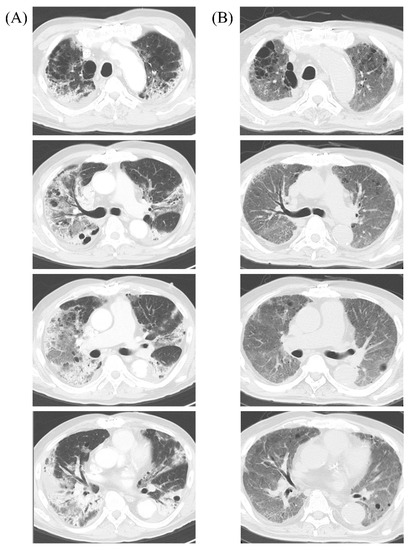

2. Case Presentation